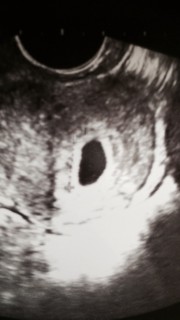

体外受精で初めて授かりました。 初めての陽性反応に、胎嚢確認。 先生も「よかったですね」と初めての笑顔を見せてくれました。 まだ6.6㎜で、心拍確認までは緊張しますが心穏やかに過ごしたいです。

体外受精で授かりました。 はじめはhCGが低く心配でしたが、なんとか胎嚢確認出来ました。 大きさはまだ測ってもらえず。 このまま順調に育ってくれるといいな。

待望の二人目。6週まで待って心拍確認できるようになってからと思ったけど我慢できず受診。 『うん、オメデタですよ~』と言われて嬉しくて何も言えませんでした。10日後には心拍見えるのを期待(*^^*)

3回の流産をして、今度こそと信じるのみ!胎嚢は予想を超えた10.1㎜でした。 次の一週間が長~い。

生理予定日に検査薬で陽性反応が出てから、5wに入るまで待って待って、やっと初検診行きました。胎嚢見えて良かった!何か質問ありますかって言われて何も思いつかなかったけど、胎嚢の大きさ教えてもらえなかったから聞けばよかった!エコーに7.5Mって出てるのは7.5ミリって事なのかな~?

5w1dで胎嚢6.5mmを確認できました。 前回は5w1dで4.2mmしかなく、流産してしまいました。 不安になり先生に大きさ大丈夫か聞いたら問題ないと言ってくださり安心しました‼︎ 次は2週間後。心拍確認できますように

胎嚢サイズは6.2ミリでした。平均5-10ミリだから大丈夫ですね、と先生に言われました。

自然妊娠で5wで胎嚢3㎜で流産経験がありました。 その後なかなか授からず、20代で体外受精に挑戦しました。 幸いにも1回で妊娠することができ、5w1dで13㎜と順調ぶりを発揮してくれています。 たくさん辛い思いをしましたが、この瞬間に今までのことを含め全て喜びに変わっています! 次は心拍確認!様々な関門がありますが、この子はきっと大丈夫だと信じています☆